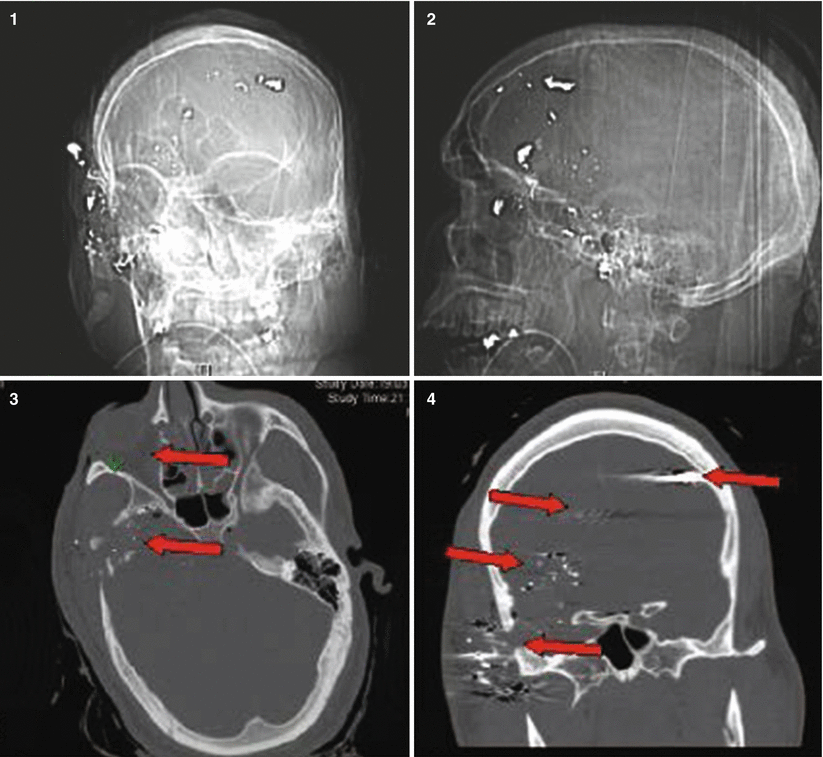

Fig. 27.2

Patient No. 2: a 23-year-old female, who sustained a solitary GSW to the head from close range. Entry wound on the R cheek, exit wound R parietal. Arrows in plates 1 and 2 of this figure illustrate the blow out fracture of the right sided calvarium as seen on CT scout images; This creates a hemispheric decompression. Arrows in plate 3 and 4 indicate the corresponding bony defect with multiple fragments as seen in bone windows of the axial CT scan. Arrows in plates 5 and 6 indicate the hemorrhagic contusion and SAH. Arrows in plates 7 and 8 indicate the hemicraniectomy site (7) and evacuated subdural hematoma site (8). Arrow in 9 points at the inserted hemicranioplasty allograft.Arrow in 10 points at the cystic portion of the encephalomalacia from the bullet tract